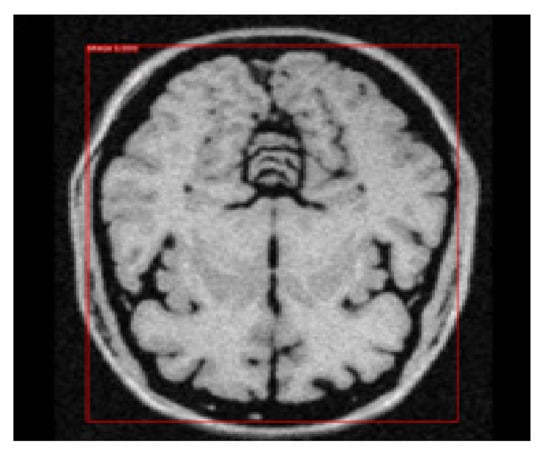

3.8. Object Detection by Applying NMS

We re-applied the function of NMS to deduce the bounding box with the highest probability from the remaining positive anchor boxes. We set the suppression threshold value using IoU ≥ 0.85 and opted for the maxima approach to retain the positive anchor box with the highest probability. This step completes the process of the first objective of this study to detect the brain encapsulated in the final remaining bounding box. Figure 11 depicts the output of the bounding box retained for object detection.

Figure 11. Retention of final bounding box with object detection.